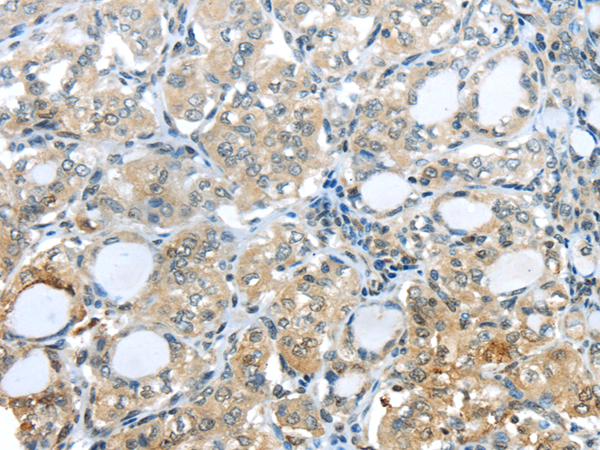

分类: 科研抗体货号: P04437别名: 42A, 18A2, CAPL, FSP1, MTS1, P9KA, PEL98应用: IHC反应种属: Human